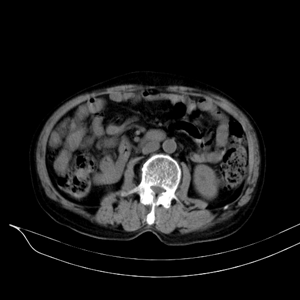

m79y自述30年前做过疝手术,20年前间断出现尿血,每次经抗炎治疗后即好转,近一月来又出现尿血但抗炎后仍尿血.现做双肾+盆腔ct:

双肾10mm扫描

盆腔5mmct扫描

该病人年龄过大故放弃了增强.ct做完后本人检查病人发现病人耻骨联合上稍偏右见一突出的包块影,质地柔软,平卧位手压后可以回缩.站立位突出明显!

膀胱三角区右侧可见较大软组织肿块,分叶状,内可见更低密度区,ct做完后本人检查病人发现病人耻骨联合上稍偏右见一突出的包块影,质地柔软,平卧位手压后可以回缩.站立位突出明显!考虑腹股沟斜疝,疝内容物为膀胱.膀胱内肿物考虑1炎性赘生物2平滑肌肉瘤(有多年血尿史,本次加重且抗炎不好转)3膀胱癌

1.膀胱内软组织肿快,有点状钙化,前列腺不大.膀胱癌.

3.双肾平扫未见异常.

1、右侧腹股沟斜疝,疝内容物为膀胱;2、膀胱右后壁肿块,考虑膀胱癌